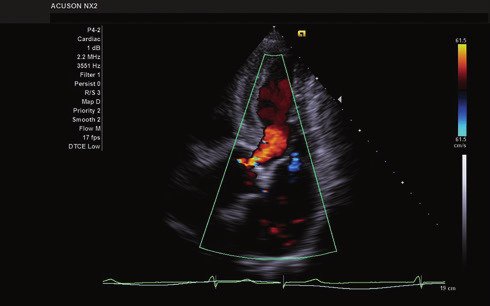

• Color, Power Angio, PW (Pulse Wave) Doppler

Das ACUSON NX2 Ultraschallsystem besitzt eine zukunftsfähige digitale Plattform mit nahezu unerreichter Bildqualität und sorgt für effiziente und zuverlässige Diagnosedaten. Die Vielseitigkeit des Ultraschallsystems wird mit einem großen kompatiblen Portfolio an Schallköpfen gedeckt, und so ist für jeden Anwendungsbereich etwas dabei. Die Bedienkonsole ist intuitiv aufgebaut und optimiert und erlaubt bis zu vier nach vorne gerichteten Schallkopfanschlüssen für eine enorme Effizienz und schnellen Workflow. So lassen sich bei der fetalen Bildgebung außergewöhnlich detailgetreue Darstellungen des Fetus im Gesicht zeigen oder durch die herausragende Farbdopplersensitivität bei der Darstellung der kleinen Gefäße des zystischen Schilddrüsenknotens kleinste Details erkennen. Weiterhin besticht das NX2 mit einfacher Aufrüstbarkeit bei wachsenden Anforderungen für Ihre zukünftigen Anwendungen und kompatible skalierbare Schallköpfe verringern ihren Kapitaleinsatz um bis zu 31 %.